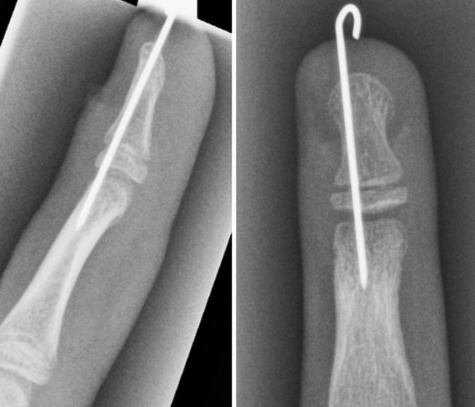

수술적 치료가 필요한 경우도 있으며, 주로 골절편의 고정과 손톱 및 연부 조직 손상 치료에 중점을 둡니다.